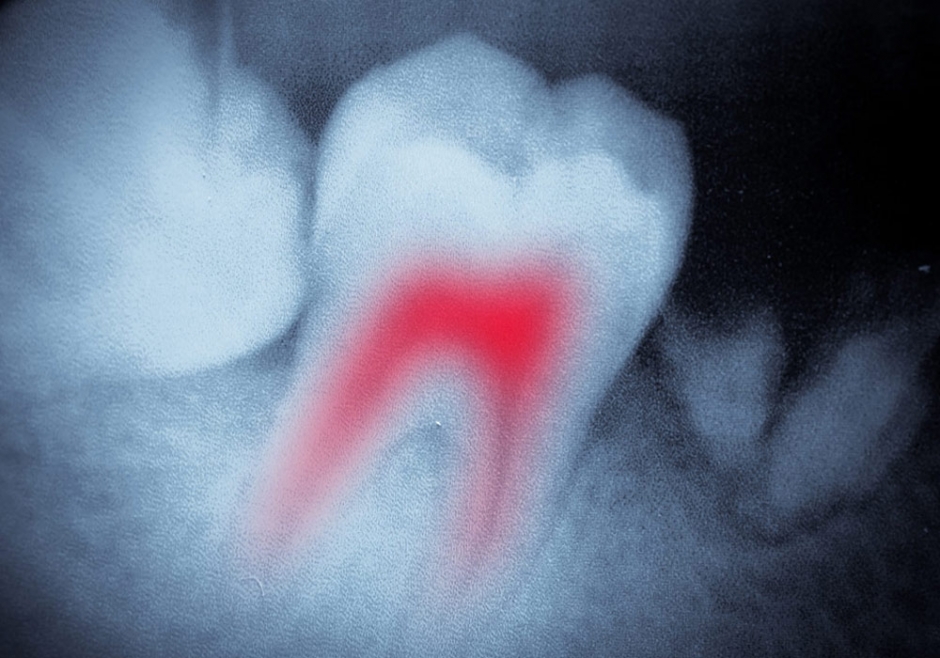

Endodontie (traitement de canal)

Lorsque le nerf de votre dent est infecté, un traitement de canal réussi vous permet de conserver votre dent plutôt que de devoir la faire extraire. En conservant votre dent naturelle, vous empêchez que les autres dents perdent leur alignement et causent des problèmes à la mâchoire. Vous évitez également de la faire remplacer par une dent artificielle.